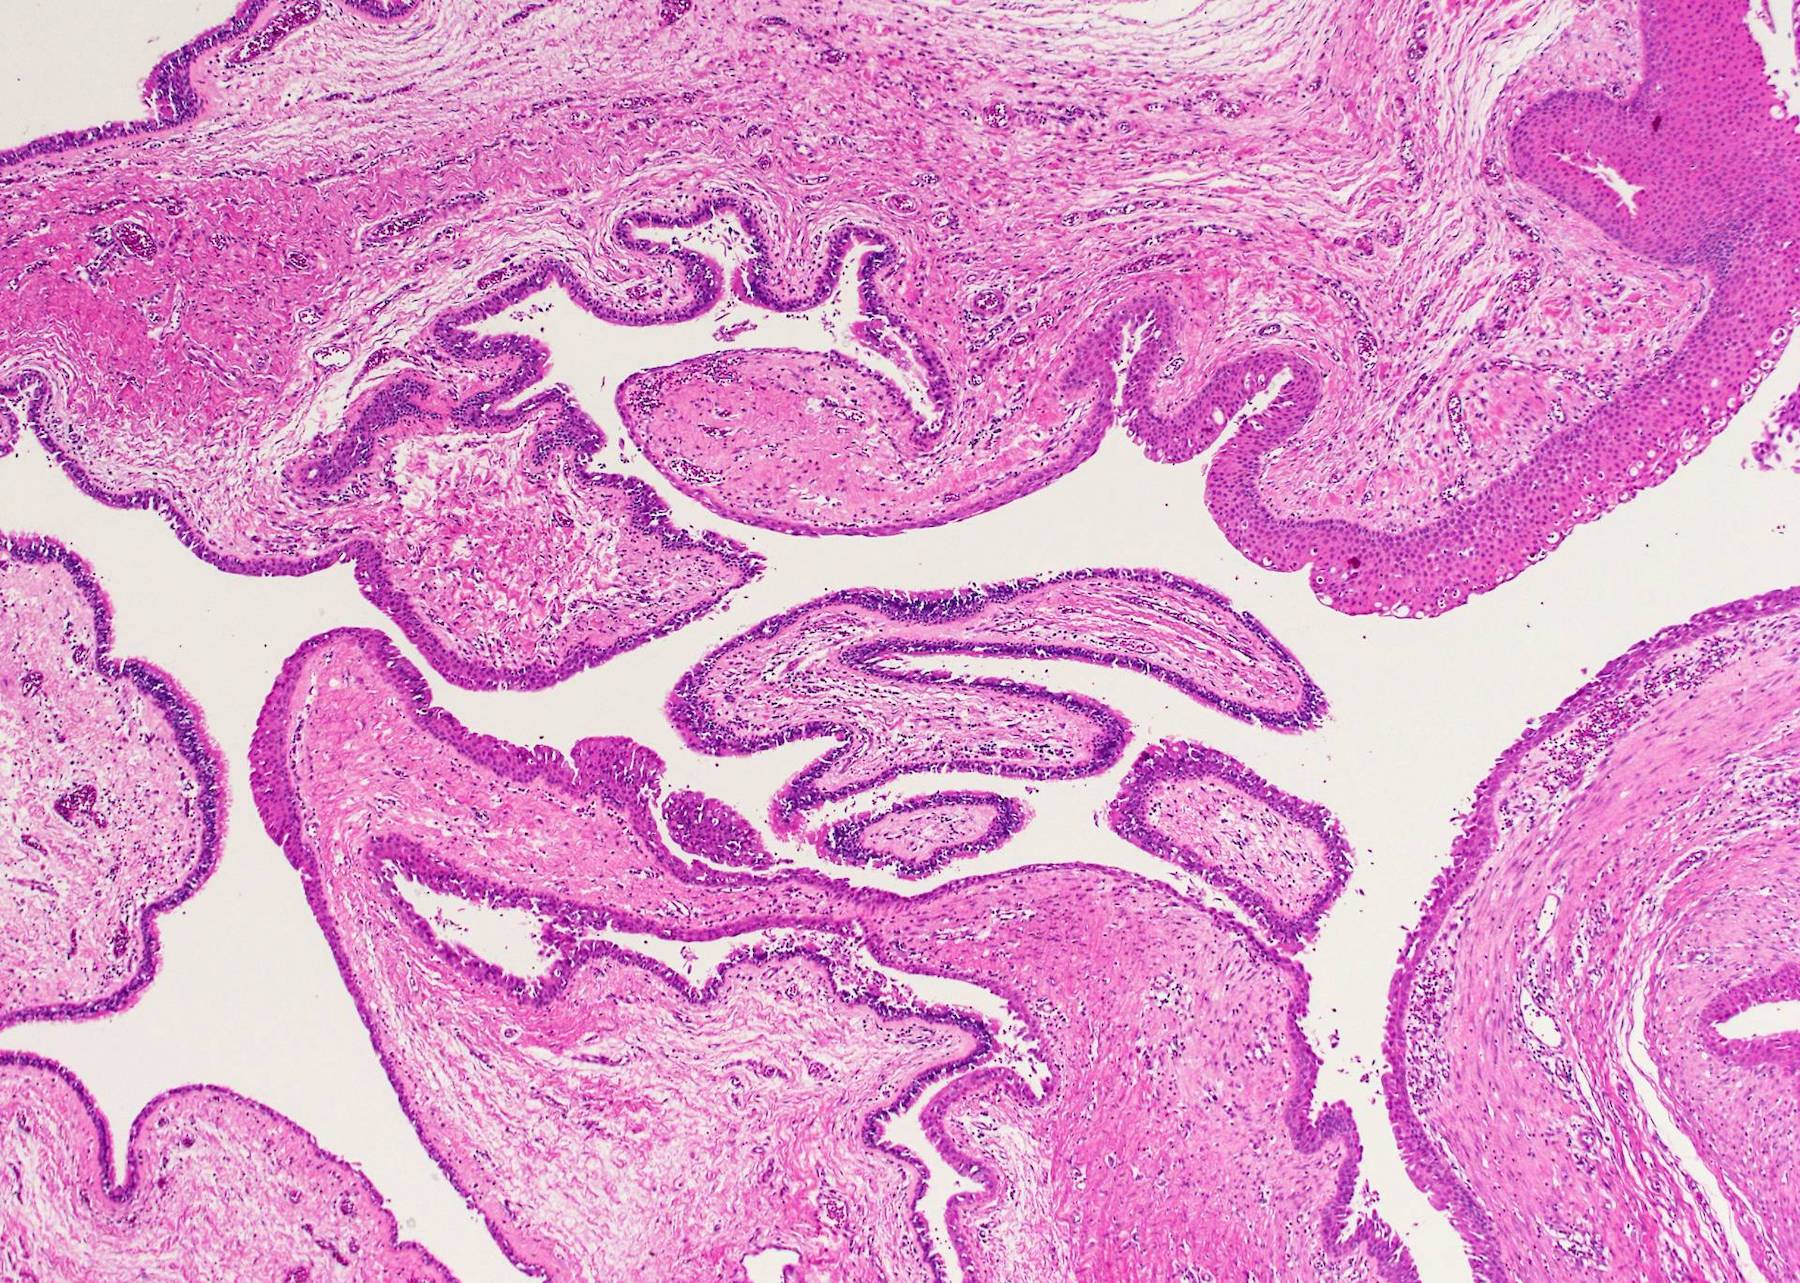

Microscopic (histologic) description

- Type of epithelial lining varies by site, and combinations of the types below can be seen in a single cyst (Head Neck Pathol 2013;7:50):

- Ciliated pseudostratified columnar (respiratory) epithelium in lower neck, perhaps due to its close proximity to upper respiratory tract

- Nonkeratinizing squamous epithelium in higher neck (near tongue and foramen cecum), also can be of metaplastic origin in inflammatory settings

- Stratified cuboidal epithelium at level of hyoid bone

- Very often the cyst is denuded of epithelium, at least focally, which reflects epithelial damage by inflammation

- Secondary inflammation is common, especially in sinus tract (J Pediatr Surg 1984;19:506):

- Intense lymphocytic infiltration, rarely arranged into lymphoid follicles

- Admixture of neutrophils (if the cyst is infected)

- Granulation tissue and fibrosis

- Thyroid follicles in the cyst / duct wall:

- Found in 30% - 60%, with higher yield on serial sections

- More common in infra- versus suprahyoid remnants, on the right paramedian side (Ann Otol Rhinol Laryngol 2000;109:1135)

- Seen in small irregular groups

- Thyroid epithelium may be normal or rarely hyperplastic or neoplastic

- Thyroid tissue often hidden by inflammation (Laryngoscope 2001;111:1002)

- Absence of thyroid tissue does not exclude the diagnosis of TGD cyst

- Mucous salivary-type glands can be found in the cyst wall, frequently in lingual and suprahyoid locations (Ann Otol Rhinol Laryngol 1996;105:996)

Microscopic (histologic) images

Contributed by Andrey Bychkov, M.D., Ph.D., Mark R. Wick, M.D. and AFIP